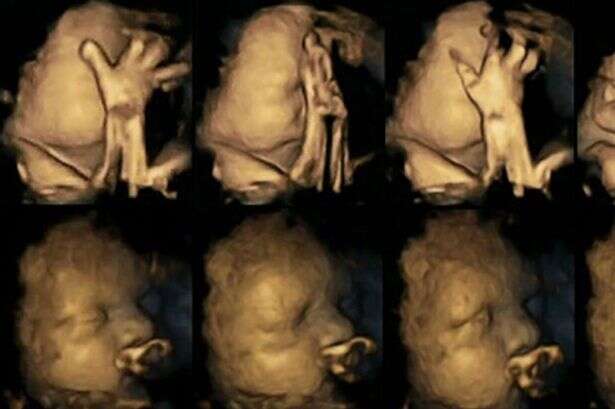

ד"ר נדיה רייסלנד עשתה שימוש בטכנולוגיה מתקדמת על מנת לנהל רישומים של מאות תזוזות של עוברים ברחם. היא עקבה אחר 20 אימהות בבית חולים במידלסבורו, אנגליה. ארבע מהאימהות עישנו מספר ממוצע של 14 סיגריות ביום. לאחר שבחנה את סריקות התמונות שיצאו בשלבי ה-24, 28, 32 ו-36 שבועות להריון, היא גלתה שהעוברים של האימהות המעשנות נגעו בעצמם והזיזו את פיהם באופן מובהק, הרבה יותר מהעוברים של האימהות הלא מעשנות.

עוברים בדרך כלל נוגעים בעצמם ומזיזים את פיהם, אך ככל שהם גדלים הם גם הולכים ונפטרים מזה ומפסיקים בתזוזות. המסקנה מהנתונים של המחקר היא שהעוברים לאימהות מעשנות לא הפסיקו את תדירות התזוזות, דבר המצביע על היעדר התפתחות של המערכת העצבית. ד"ר רייסלנד מדגישה: "צריך להרחיב את המחקר בכדי לאשש את התוצאות שלו".

החוקרת מאמינה שההבדלים בין התצלומים, שמראים הבדלים ברורים, יכולים לסייע לאימהות להפסיק לעשן. עם זאת, היא מתנגדת לחלוטין להפוך אימהות שלא מצליחות לעשן לאנשים רעים והדגישה כי חייבים לעזור להם להפסיק ולתת להם תמיכה ראויה. למרות תוצאות המחקר כל התינוקות שהשתתפו בו נולדו בגודל ומשקל תקינים.

עמית המחקר של ד"ר רייסלנד, פרופסור בראיין פרנסיס אמר: "טכנולוגיה יכולה לסייע לנו לראות מה שהיה מוסתר, בכדי לחשוף כיצד עישון יכול להשפיע על התפתחות עוברים כל זאת בדרכים שלא האמנו, שיכולות להיות. תוצאות המחקר הזה הן הוכחה להשפעה השלילית של עישון על הריון".